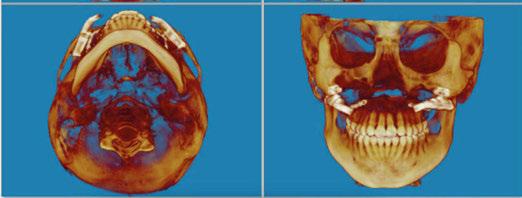

The CBCT image revealed several findings. First, it was apparent that a periapical radiolucency (PARL) existed in association with the overlapping mandibular incisors (Figures 4A – 4C). Figure 4A shows tooth No. 24 with compromised facial alveolar support, while figure 4C shows tooth No. 25 with a greater amount of visible facial bone. In figure 4E, tooth No. 27 is proclined and has compromised facial alveolar support. Lastly, a second PARL was noted surrounding tooth No. 8 (Figure 5).

Figure 3: Panoramic X-ray taken with diagnostic records on December 17, 2020 Figures 5A-5B: 5A. Shows the sagittal view of tooth No. 8 with associated PARL. 5B. Shows the coronal view of tooth No. 8 with associated PARL Figures 6A-6B: 6A. Shows extractions of tooth Nos. 5 and 12. 6B. Shows extractions of tooth Nos. 24 and 27 Figures 4A-4D: 4A. Shows the sagittal view of tooth No. 24 with what appeared to be an associated PARL. Figure 4B shows the PARL from an axial view centered in the mandibular anterior region. Figure 4C shows tooth No. 25 in the sagittal view, closely associated with the PARL. Figure 4D shows the 3D model of the maxillary and mandibular arches. Figure 4E shows tooth No. 27 in the sagittal view A. B. D. C. E. A. A. B. B.